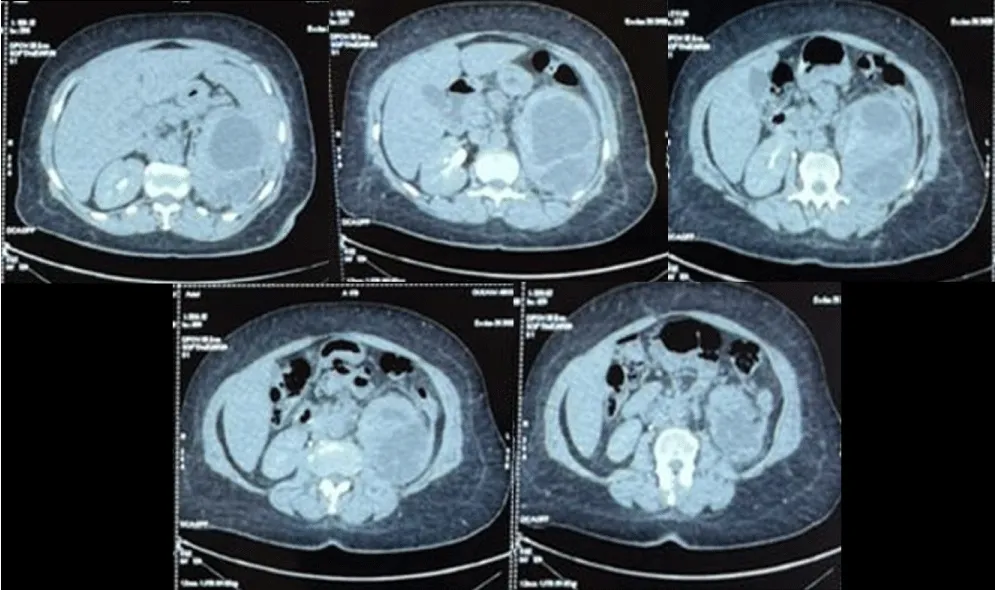

A subsequent Computed Tomography (CT) imaging of the abdomen and pelvis revealed an enlarged left kidney with a 9 × 6 cm multiloculated subcapsular collection characterized by a thick, enhancing wall with internal septations, causing a ‘mass effect’ that compressed the collecting system without causing downstream ureteral obstruction. Two non-obstructive calculi were identified in the inferior pole, measuring 9 millimeters and 3 millimeters, respectively, with attenuation of 274 Hounsfield Units (HU), consistent with calcium-containing stones. It is noteworthy that there was an absence of evidence indicative of collecting system dilatation or ureteral obstruction (Figure 1).

Figure 1: Axial contrast-enhanced CT scan of the abdomen. The images reveal an enlarged left kidney with a 9 × 6 cm multiloculated subcapsular collection. This collection causes significant compression of the renal parenchyma and lamination of the calyceal groups. No evidence of collecting system dilatation or ureteral obstruction is noted.